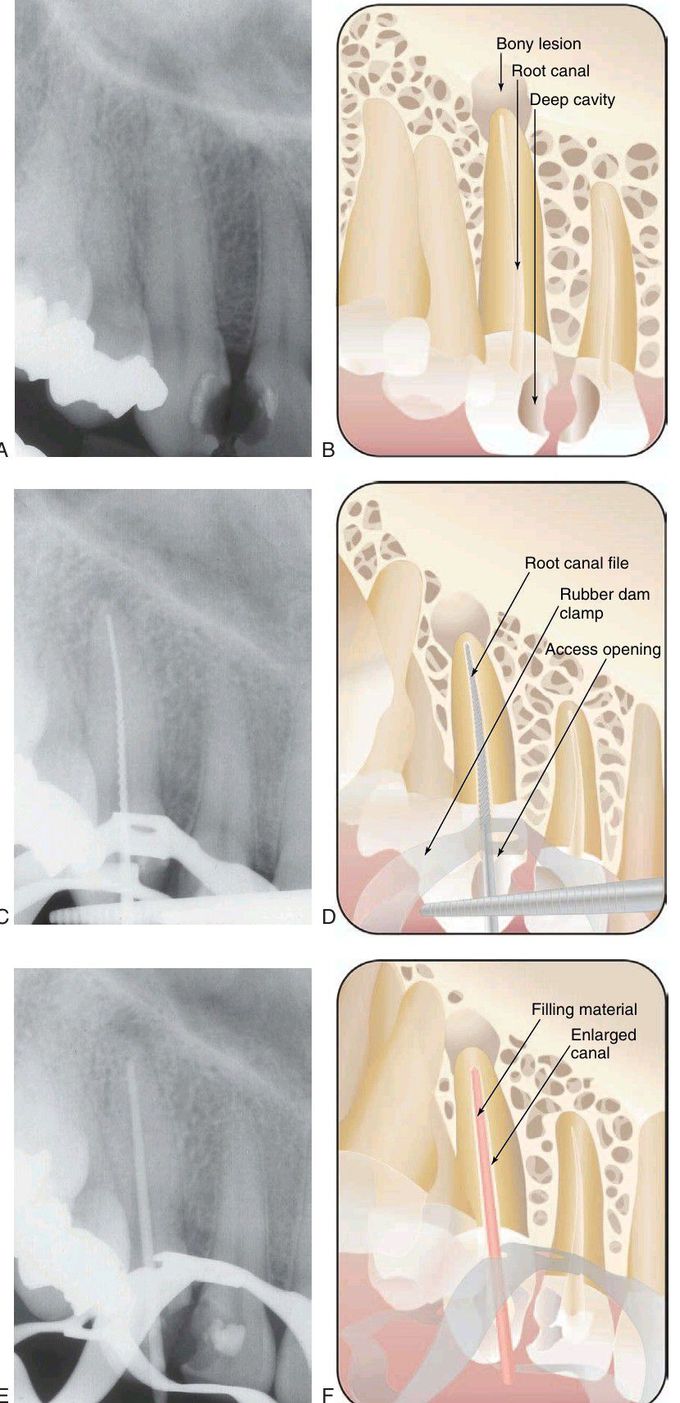

Series of radiographs and illustrations demonstrating root canal treatment and restoration of a maxillary canine. A-B, Maxillary canine with periradicular lesion of endodontic origin. C-D, Endodontic file corresponding to length of canal; isolation with rubber dam throughout procedure. E-F, Endodontic filling material placed after cleaning and shaping of canal. C